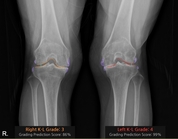

중앙대학교병원이 ‘2025년 AI 바우처 지원사업’ 주관기관으로 선정돼 의료 인공지능(AI) 기술을 임상 현장에 본격 도입했다. 중앙대병원은 AI 기반 의료 솔루션 전문 기업 코넥티브와 컨소시엄을 구성해, 무릎 관절염 진단 보조 솔루션 '코네보 코아(CONNEVO KOA)'를 병원 영상저장전송시스템(PACS)에 연동했다. 국내 대학병원에서 AI 기반 무릎 관절염 진단 보조 솔루션이 PACS에 적용된 것은 이번이 처음이라고 22일 밝혔다. '코네보 코아(CONNEVO KOA)'는 무릎 X-ray 영상을 분석해 관절염 심각도를 ’K-L(Kellgren–Lawrence) 등급’으로 판정하고, 골극과 관절 간격을 시각화해 제공한다. 이를 통해 진단의 일관성을 높이고 환자와 상담 시 유용한 시각자료로 활용할 수 있다. 중앙대병원은 이번 사업을 통해 영상 데이터셋 구축과 환자 평가 방법 개발을 추진, 진료의 질 향상과 의료진의 업무 효율화를 꾀할 계획이다. 영상의학과 김수진 교수가 총괄 책임을 맡아 솔루션의 임상적 유효성을 검증하고, 시스템 고도화를 주도한다. 공동 연구자인 정형외과 김성환 교수는 “AI 솔루션이 관절염 상태를 직관적으로 보여줘 환자 이해도가 크게 향상